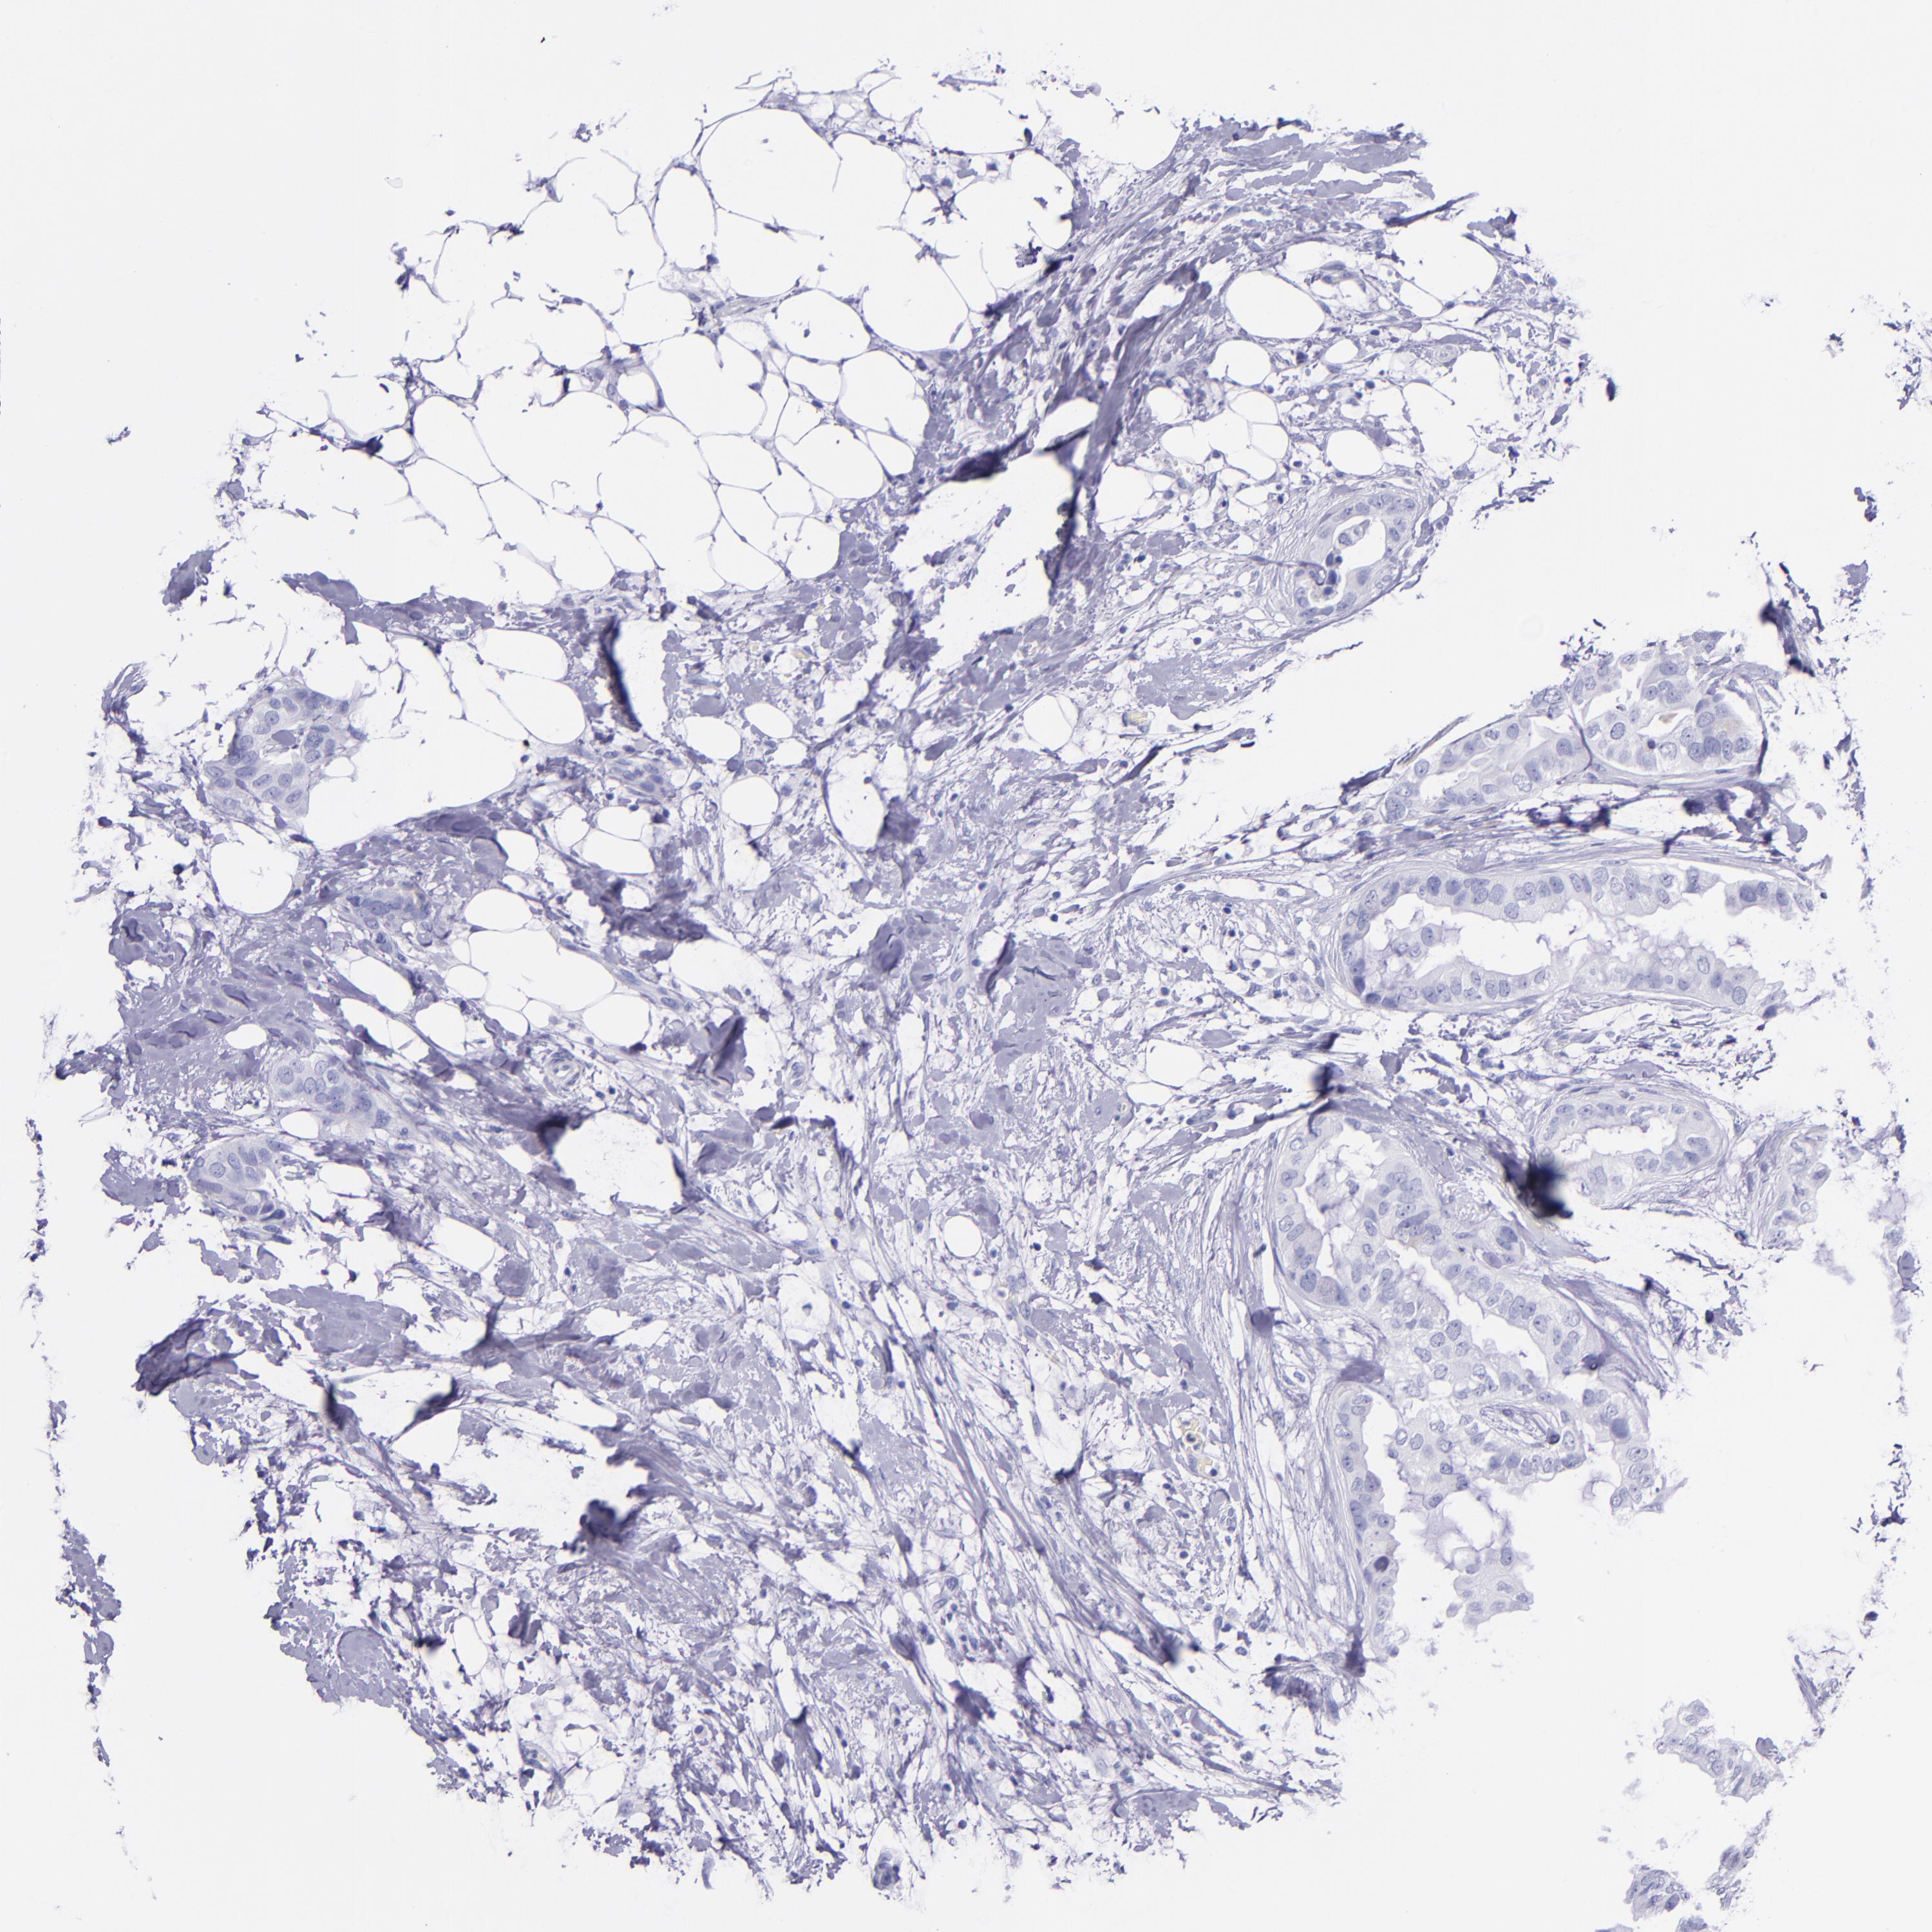

CANCER BREAST CANCER Show tissue menu

Breast cancer

Human cancer